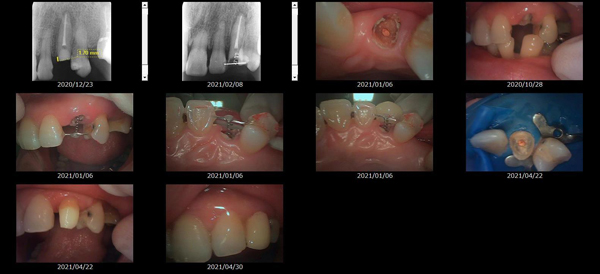

救歯MTM

虫歯が大きくて残せない歯、転倒などの事故により歯が根の深いとこで折れてしまったなどで、抜かざるを得ない歯を、骨の中に埋まっている健全な根を、骨の上に矯正的に引き上げることで、その歯を抜かず温存、救歯できる可能性のある治療方法です。

この特別な診療である救歯MTMは、以下のような特徴があります。

①健全な歯を、歯肉から見える位置にまで引き上げることで

根の治療の成功率を上げることが出来る。唾液には沢山の細菌がいます。唾液が入らない環境での根の治療を(神経の治療)を行うことで神経の治療、根の治療の成功率は格段と上がります。

②骨の上にある歯と土台で支える被せもの製作できる。

被せものを土台だけに頼ることなく、引き上げた健全な歯でも支えることで、歯への被せ物がしっかりと装着できるようになる。

③抜かずに歯を活かすことで、隣の歯を削るブリッジやインプラントにしないで済むことがある。

歯を矯正的に引き上げることで、その歯を救歯できるだけでなく、隣の歯を削るなどの侵襲を回避できる場合がある。

救歯治療と審美性の両立

当院では様々な治療の基礎に審美と機能の両立というテーマがあります。

リスク

- > 歯を矯正的に引き上げることで、骨の中の根の長さは短くなりますが、その短さでも安定するという診断をした場合のみ施術になります。 残せる歯、根の長さが短い場合は、この救歯MTMの治療対象とならない場合がございます。

- > 治療期間が数か月~1年に及ぶ場合がある。

- > 費用が自費診療 44,000円 ~ 66,000円

- > 救歯MTMは救歯BTAセラミックと併用治療が必要な場合があります。

症例